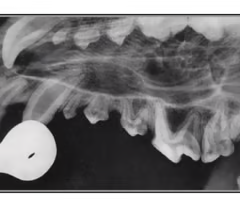

What view is this and what is the pathology?

Oblique - tooth route abscess

Is the yellow arrow a pathology?

No- common in young horses w/ teeth still growing